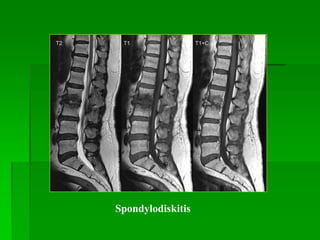

Spondylodiskitis

Các dấu hiệu thoái hóa cột sống:

 Đốt sống: thân sống giảm bề

cao,có gai xương, mặt thân sống

kém đều; mấu khớp thoái hóa (gai

xương, phì đại), bất thường tín

hiệu thân sống (Modic I,II,III).

 Đĩa đệm: giảm bề cao, mất nước

(tín hiệu thấp trên T2W), khí trong

đĩa đệm, rách bao xơ, lồi hay thoát

vị đĩa đệm.

THOÁI HÓA CỘT SỐNG

Loại

thoái

hóa

Tín

hiệuT1

W

hiệu

T2W

Modic

type I

TH

viêm

Thấp Cao

type II

mỡ

Cao Cao

type

III

xơ

Thấp Thấp